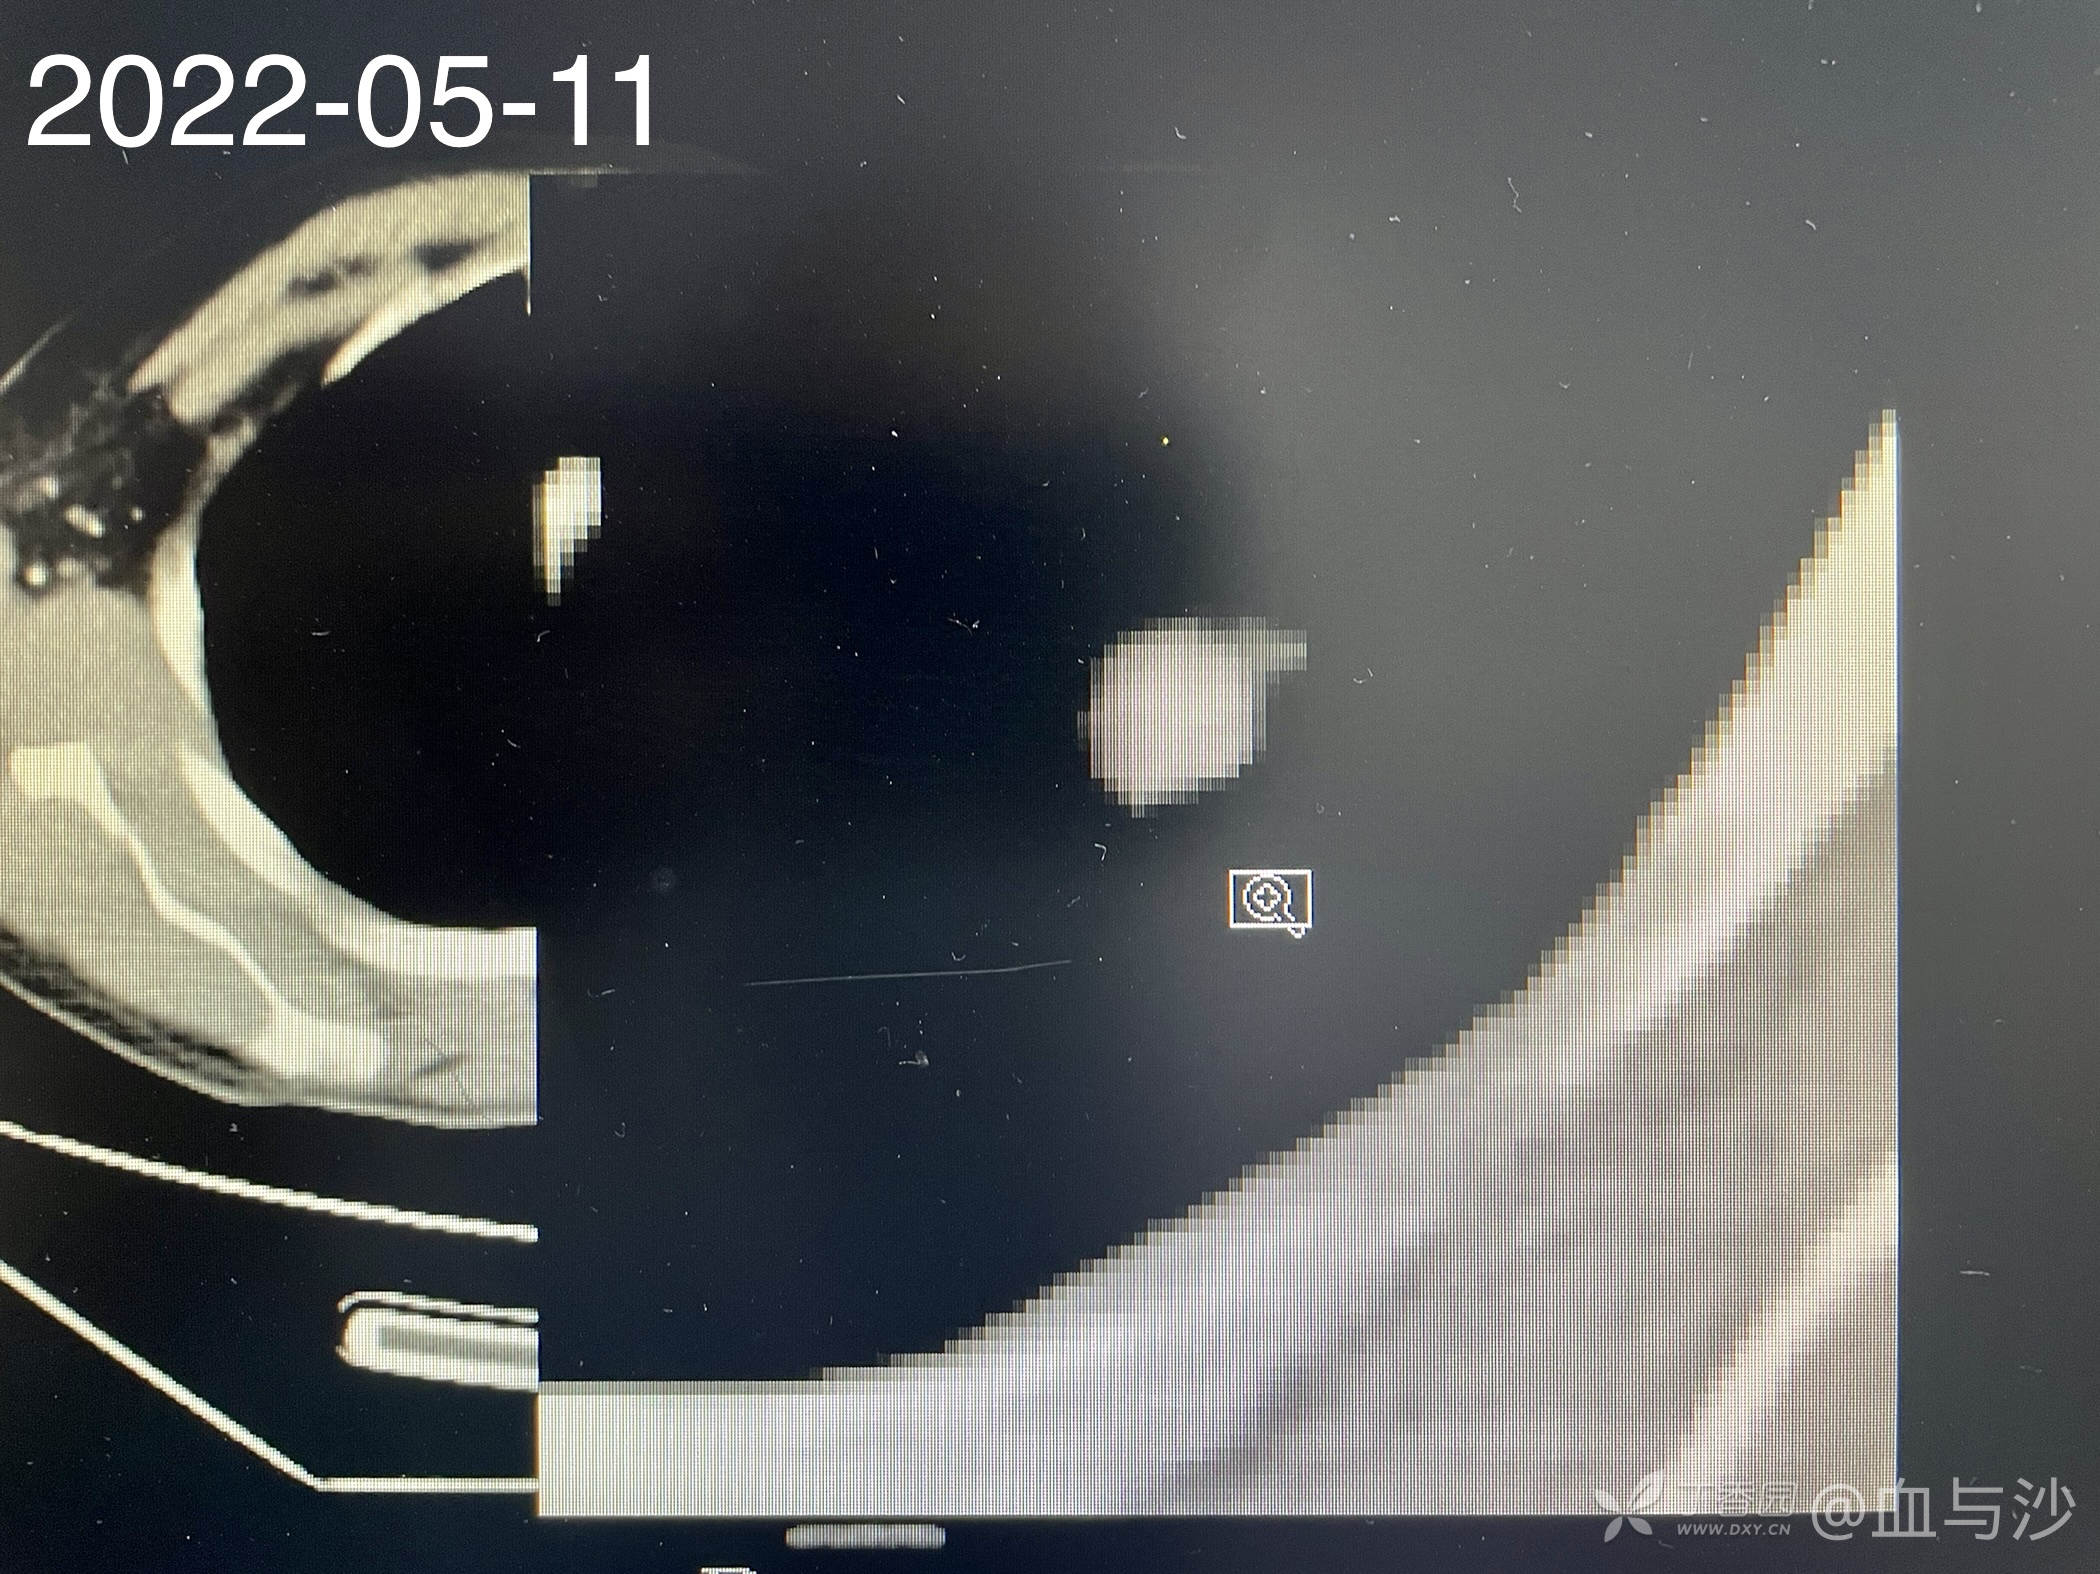

以下是今年5月的CT影像:

病人女,60岁,去年4月底因咳嗽发热入院,诊断支气管扩张伴感染(结核各项检查阴性,病人平时也无潮热盗汗),予抗感染对症处理。当时CT片左肺上叶有一磨玻璃样影。今年5月病人再次咳嗽发热入院,续按照支扩伴感染处理,但CT显示去年的磨玻璃影成了一约1.5cm的实性结节。

大伙帮看看呢,除了肿瘤还有没有其他可能🤔